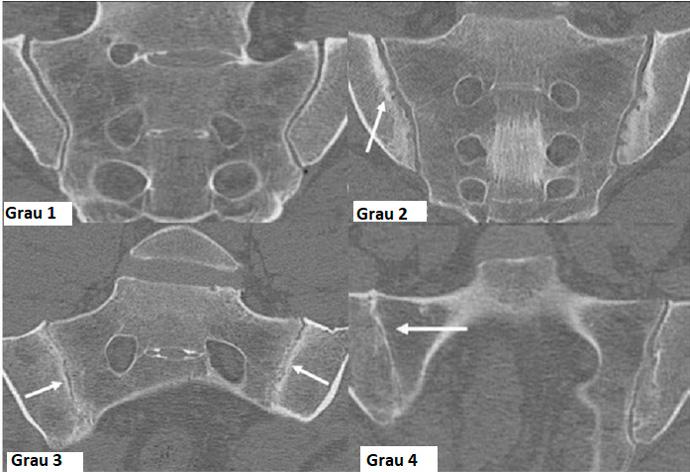

Exemplos de exames de tomografia computadorizada, que exibem diversos graus de Sacroileíte.

• Grau 1 – normal

• Grau 2 – erosões e esclerose óssea

• Grau 3 – redução do espaço articular e anquilose parcial

• Grau 4 – Sinostose completa